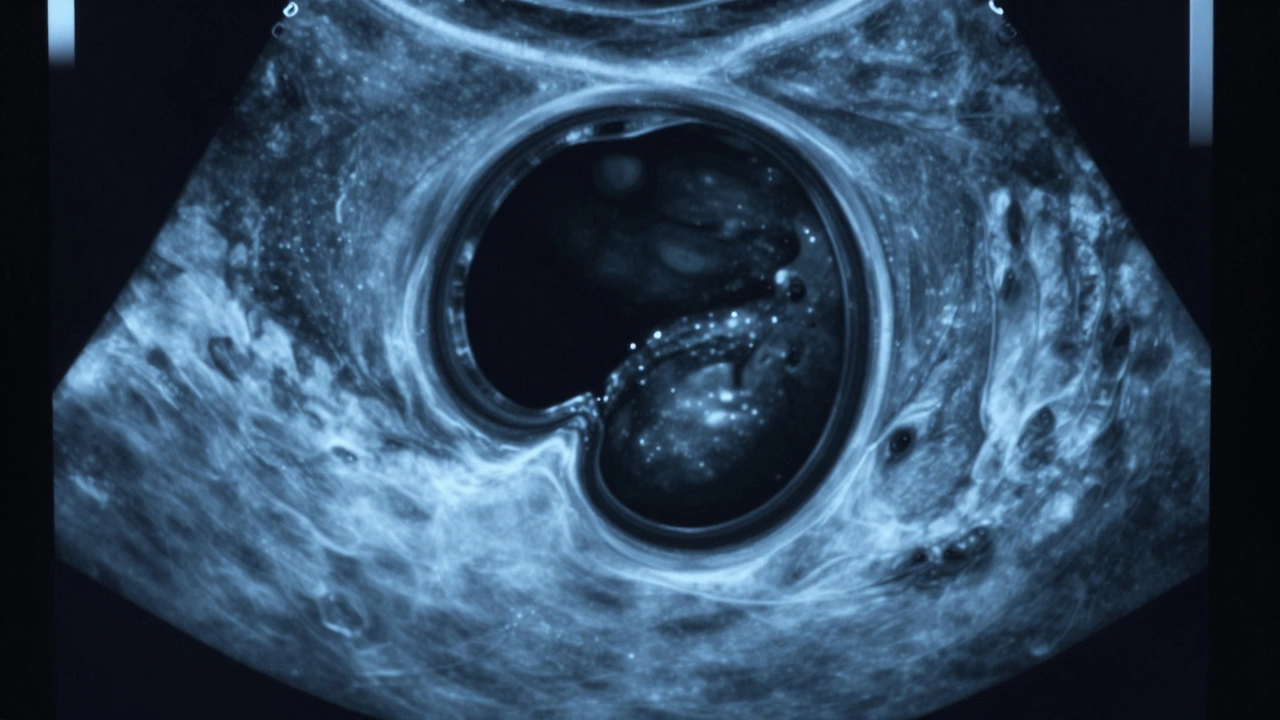

Киста - это полость, заполненная жидкостью. На УЗИ она выглядит как чёрный или тёмно-серый круг или овал с чёткими границами. Внутри - однородная тёмная область, потому что жидкость не отражает ультразвук. Если киста простая, то она не имеет перегородок, не содержит включений, не имеет кровотока. Такие кисты - почти всегда доброкачественные. Например, простая киста яичника или почки встречается у каждой пятой женщины и почти никогда не требует лечения.

Бывают и сложные кисты. В них могут быть перегородки, мелкие включения - как будто внутри есть мелкие комочки. Это не значит, что это опухоль. Это может быть кровь, сгустки слизи или остатки тканей. Но такие кисты требуют наблюдения. Врач скажет: «Повторите УЗИ через 3 месяца» - чтобы убедиться, что ничего не меняется.